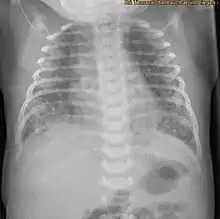

| X-ray showing the extent of lung epithelial damage in response to meconium seen in neonates with meconium aspiration syndrome. | |